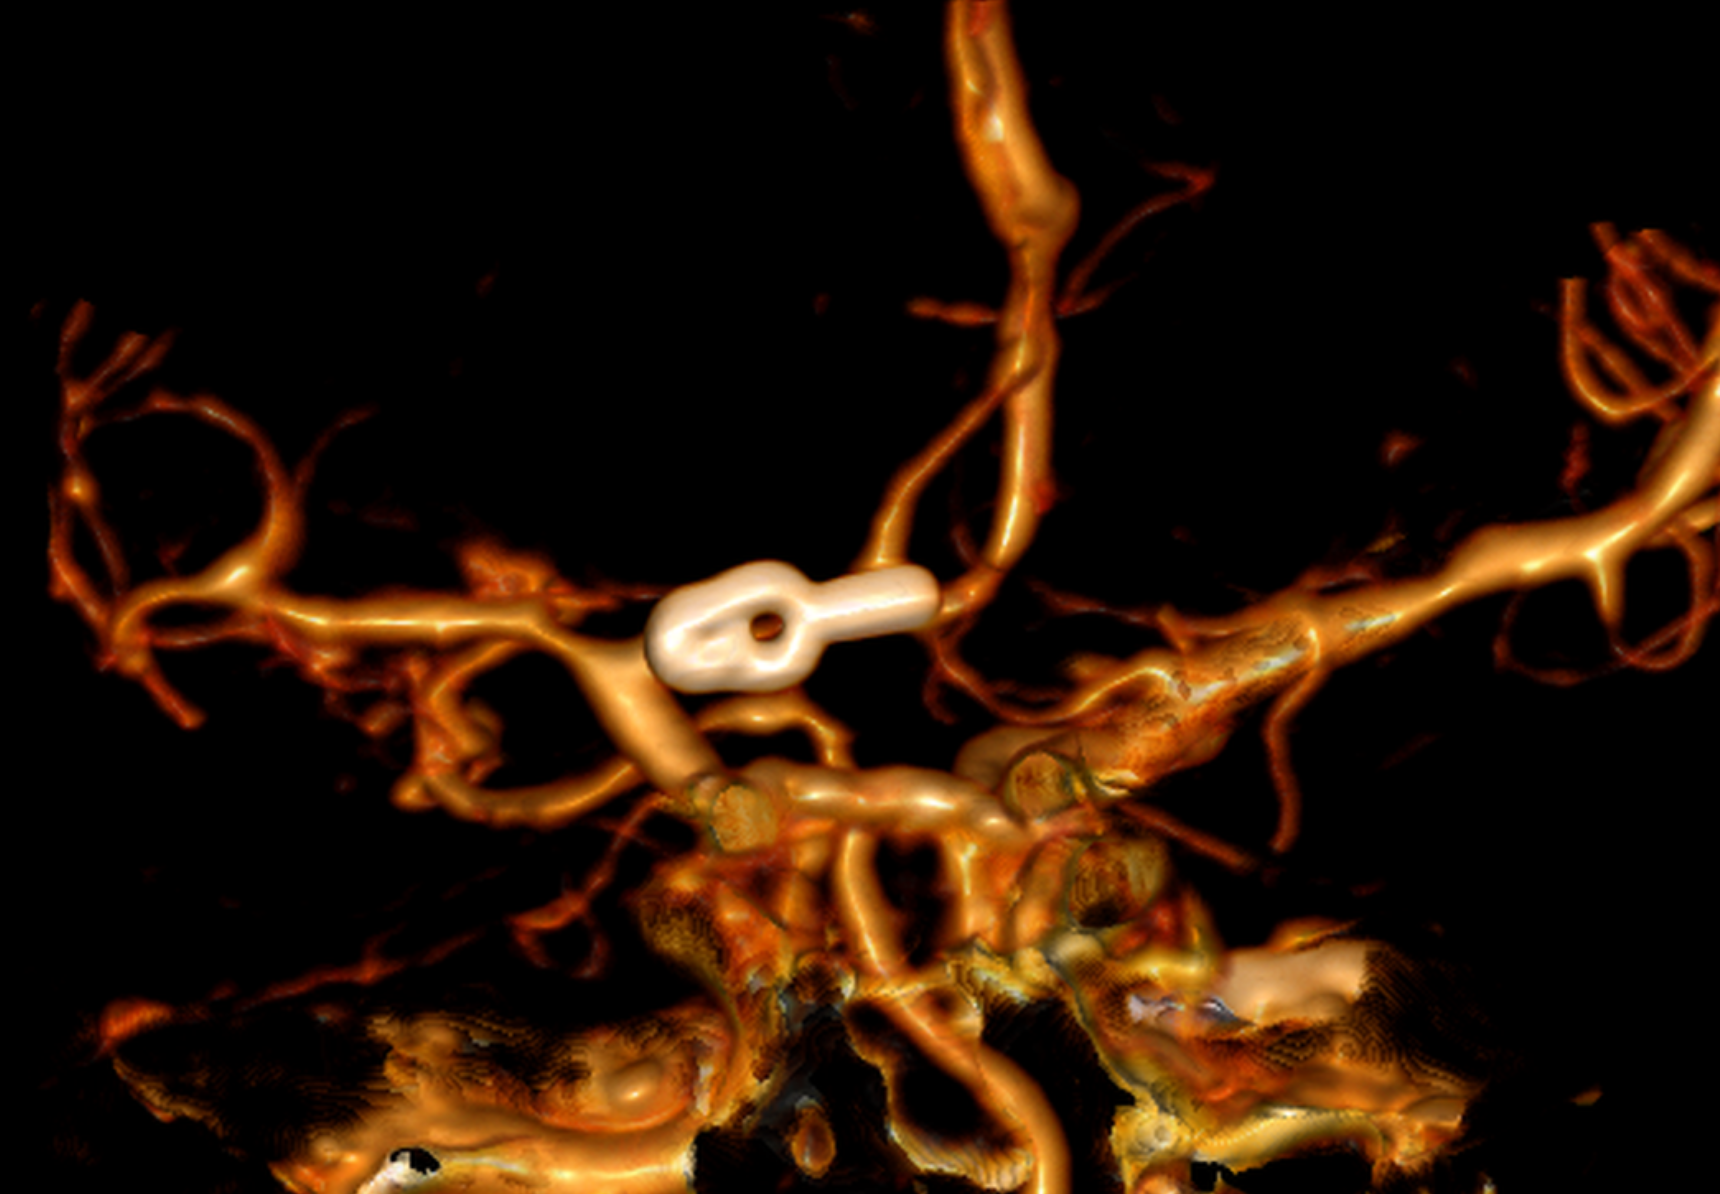

Surgical clipping (resolution)

A small incision is made behind the hairline and a piece of bone is removed to allow access to the aneurysm. The aneurysm is identified under microsurgical vision, with its branches and one or more clips applied externally to its neck. When the aneurysm is healed, the bone is replaced with special titanium plates and the incision is closed.

Clipped aneurysm

Aneurysm clip and support